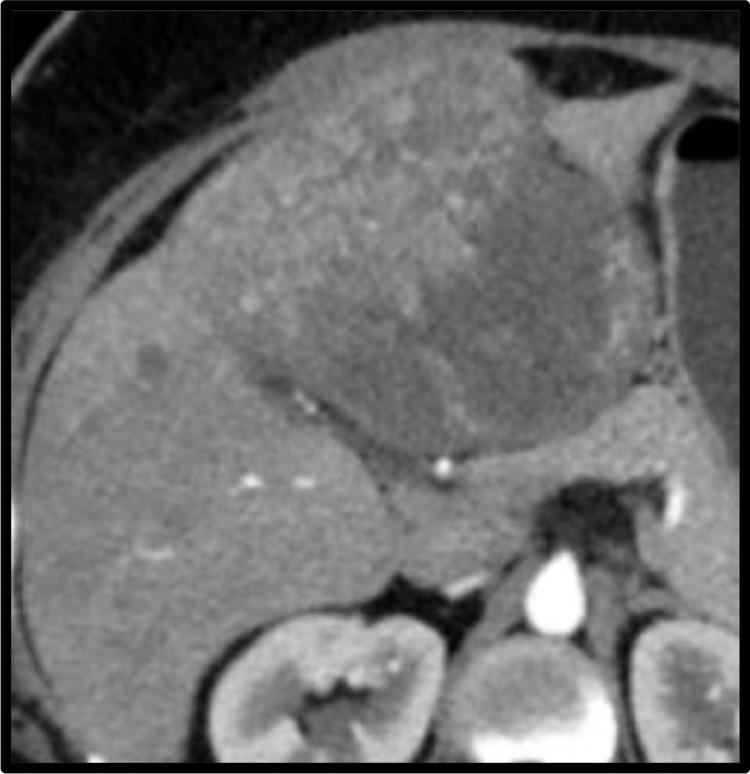

Liver is the most common site for neuroendocrine metastasis. However, primary neuroendocrine tumor is a rare focal hepatic lesion with a better prognosis than hepatocellular carcinoma and other malignant hepatic lesions. We present a case of primary hepatic neuroendocrine tumor in a 38-year-old female patient with a radiological diagnosis of atypical focal hepatic lesion, and a confirmed diagnosis on histopathology. Few radiology features like predominant cystic component with absence of focal lesion at any other site, aids the imaging diagnosis of primary hepatic neuroendocrine tumor.

摘要

肝脏是神经内分泌转移最常见的部位。然而,原发性神经内分泌肿瘤是一种罕见的肝脏局灶性病变,其预后比肝细胞癌和其他肝脏恶性病变要好。我们报告一例38岁女性原发性肝脏神经内分泌肿瘤病例,该病例经放射学诊断为非典型肝脏局灶性病变,并经组织病理学确诊。一些放射学特征,如以囊性成分为主且其他任何部位均无局灶性病变,有助于原发性肝脏神经内分泌肿瘤的影像诊断。